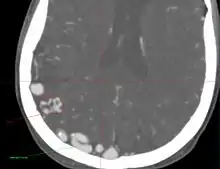

- Originally described by Luschka and Virchow in the mid 1800s, AVMs are abnormal communications between arteries and veins without the normal capillary flow.

- Abnormal communication between artery and vein, with disproportionate and unbalanced hydrodynamic stress across them. The direct connection between the arterial and venous systems exposes the venous system to abnormally high pressures and results in the formation of enlarged feeding vessels and enlarged draining venous structures.

- Point of abnormal communication is known as the nidus

- Hemorrhage is the most common reason for presentation (~50%). It is often associated with the acute onset of a severe headache that may be described as “the worst headache of my life”. Depending on the location, it may also be associated with a new neurologic deficit. Seizure can be seen in about 45% of patients, headache in 33%, and neurologic deficit in 20%.